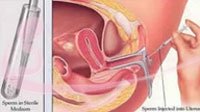

IUI

Intrauterine insemination is a procedure that enriches sperm quantity and quality by laboratory methods and includes placement of the same into mother’s womb using a special cannula. The day for this procedure is selected by the doctor after serial ultrasound to determine the most fertile day of your menstrual cycle, semen obtained by the partner is washed to remove impurities and best sperms are selected by laboratory methods to increase the concentration of good sperms capable of fertilizing the ovum. This ensure that a large number of healthy sperms get to reach the ovum thereby increasing the chances of pregnancy. Intrauterine insemination is a procedure that enriches sperm quantity and quality by laboratory methods and includes placement of the same into mother’s womb using a special cannula. The day for this procedure is selected by the doctor after serial ultrasound to determine the most fertile day of your menstrual cycle, semen obtained by the partner is washed to remove impurities and best sperms are selected by laboratory methods to increase the concentration of good sperms capable of fertilizing the ovum. This ensure that a large number of healthy sperms get to reach the ovum thereby increasing the chances of pregnancy. |

Intrauterine insemination may be selected as initial fertility treatment by your doctor for the following conditions:

- Unexplained infertility

- Idiopathic infertility

- Cervical abnormality

- Sexual dysfunction

- Requirement of donor sperm

- Low sperm count

- Decreased sperm motility